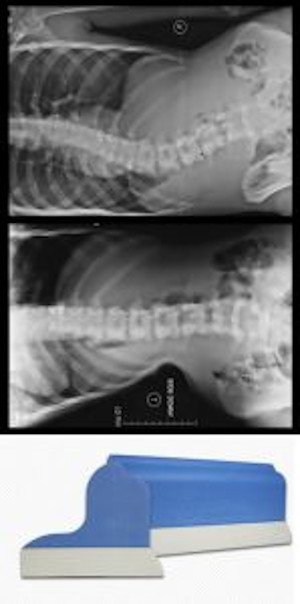

ScoliRoll – Effective Scoliosis Treatment Aid for Improved Flexibility and Stabilization

See What 20 Minutes a Day Laying on A Piece of Foam Can Do For Your Curves

ScoliRoll® is a scoliosis treatment aid developed by Denneroll Industries and ScoliCare, designed to complement other therapies like exercise programs and bracing. It utilizes a patented Denneroll peak to de-rotate and straighten scoliosis curves, allowing for muscle and ligament stretching as well as spinal stabilization exercises. ScoliRoll also serves as a diagnostic tool to assess scoliosis curve flexibility, aiding in determining potential correction levels. The device is available in versions tailored for lumbar and thoracic scoliosis curves.

ScoliRoll: A Reliable Aid for Increasing Spinal Flexibility

What is ScoliRoll?

ScoliRoll is a specialized scoliosis treatment device created by Denneroll Industries in partnership with ScoliCare. This innovative aid is designed to complement other scoliosis therapies, such as the physiotherapeutic scoliosis specific exercsises and fully customized to you ScoliBraces. Its patented Denneroll peak generates a precise bending force that helps de-rotate and straighten the spine, facilitating muscle and ligament stretching and enabling spinal stabilization exercises while maintaining a corrected position.

Additionally, ScoliRoll® serves as a diagnostic tool to evaluate the flexibility of scoliosis curves, providing clinicians with insights into the potential extent of curve correction achievable through rehabilitation or bracing.

How does it work?

The ScoliRoll utilizes its patented Denneroll peak to assist in:

- Straightening scoliosis curves

- De-rotating the spine

- Stretching ligaments, which is particularly beneficial for patients with stiff scoliosis curves to enhance spinal flexibility